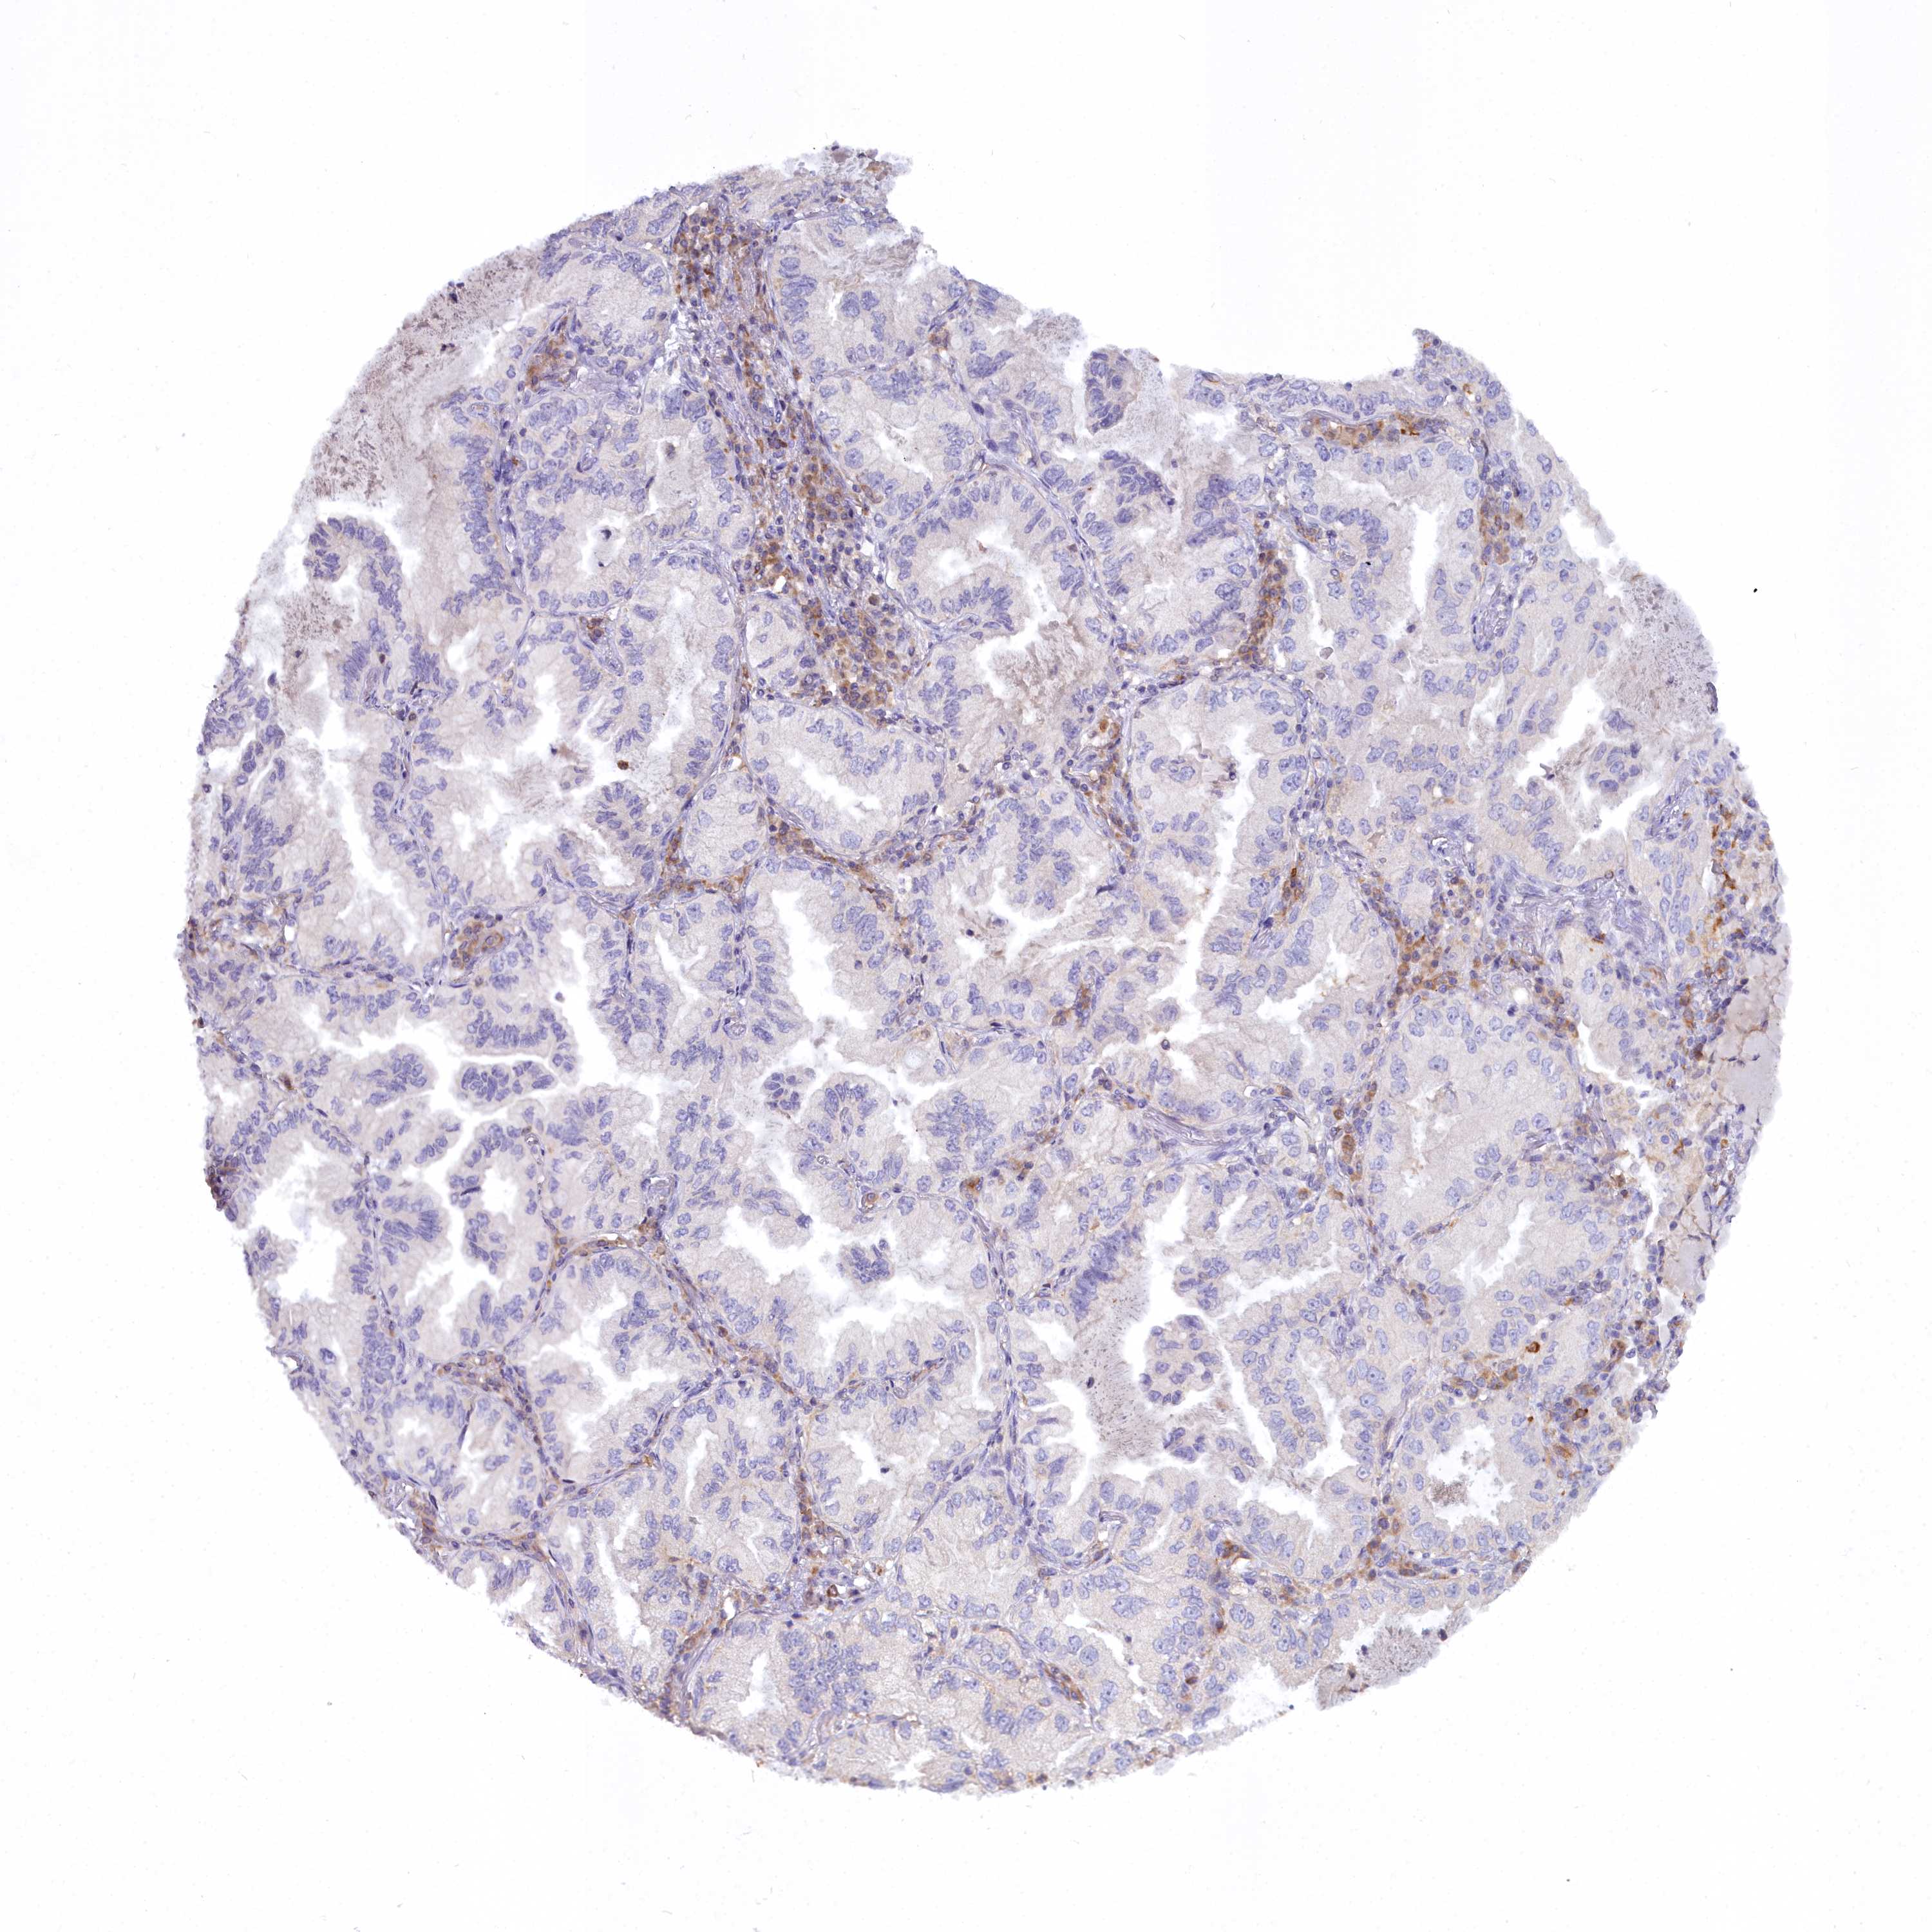

CANCER LUNG CANCER Show tissue menu

LUAD TCGA LUAD VALIDATION LUSC TCGA LUSC VALIDATION PROTEIN LUAD CPTAC PROTEIN LUSC CPTAC PROTEIN EXPRESSION

ANTIBODIES

AND

VALIDATION